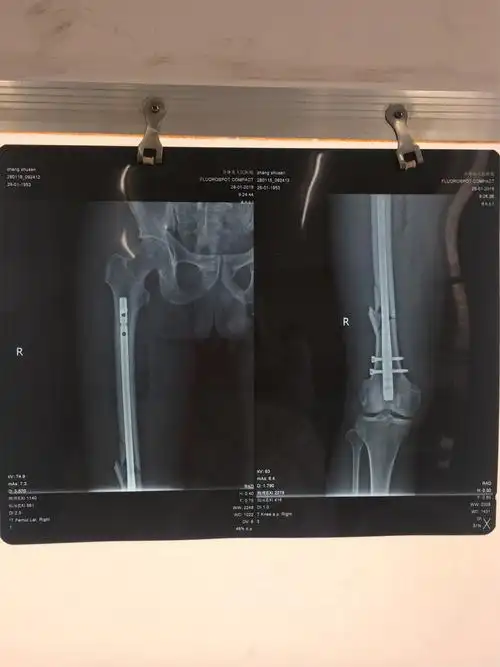

骨科顺利完成我院首例倒打钉内固定术